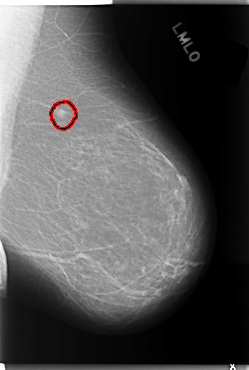

C_0114_1.LEFT_MLO

LEFT_MLO LINES 5912 PIXELS_PER_LINE 3984 BITS_PER_PIXEL 12 RESOLUTION 50 OVERLAY

FILE: C_0114_1.LEFT_MLO.OVERLAY

TOTAL_ABNORMALITIES 1

ABNORMALITY 1

LESION_TYPE MASS SHAPE IRREGULAR MARGINS MICROLOBULATED

ASSESSMENT 5

SUBTLETY 5

PATHOLOGY MALIGNANT

TOTAL_OUTLINES 1

BOUNDARY